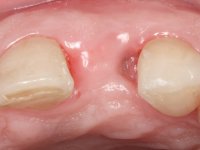

Female patient, 47 years old non-smoker. Tooth 1.3 with endodontic treatment and a cast post and core, rehabilitated with a provisional crown. The two upper lateral incisors are conoid and of small dimension. Tooth 2.2 presents mobility, in agreement with a significant bone reabsorption between teeth 2.1 and 2.3. The two central incisors are separated by a 3 mm diastema and tooth 2.3 presents a crossed occlusion with the opposing tooth. There is also an absence of some posterior teeth and reasonable oral hygiene. In the second intervention performed 8 years later, it was verified that the upper central incisors were chromatically darker and had a longitudinal groove in the enamel which, being pigmented, aesthetically compromised the smile. The work performed in the first phase of the treatment was competent, aesthetically and functionally. Finally, one year after the last intervention, the patient complained of a fracture on the veneer placed on tooth 2.1, probably as a result of being in contact with the abutment of the implant. The rigidity of implant ankylosis may have been the cause of this fracture. I have observed other instances of this type of fracture in identical clinical situations. The veneer of tooth 1.2 was aesthetically compromised and the dental structure itself had small caries and, therefore, its replacement would be recommended.

Treatment began with re-preparation of the cast post and core, with the purpose of placing the cervical finishing lines with an intra-sulcular location and simultaneously making a suitable temporary crown. With a very simple orthodontic treatment, the diastema was closed between the upper central incisors, and this position was stabilized with a wire placed on the palatal surface of the central, functioning as containment. Later, a slow orthodontic traction of tooth 2.2 was attempted, in order to reduce, although very slightly, the vertical bone loss in this area. At the end of the traction, tooth 2.2 was extracted and the area was provisionally rehabilitated with a composite resin crown bonded to the adjacent teeth. A dental implant was placed in the area of tooth 2.2 and the temporary crown was again bonded to resin, provisionally rehabilitating the patient during osseointegration. In tooth 1.3 a gingivectomy with an electric scalpel was performed, with the intention of raising the cervical level of 1.3 achieving greater harmony with tooth 2.3. Stabilized soft tissues were impressed using the open tray technique with putty and light addition silicones. Collection of the color of both the dental component and soft tissues was done by the ceramist in the office. In the laboratory, the impressions were transferred to plaster and gave origin to work models that were properly analyzed. It was decided to assemble a metal-ceramic abutment screwed onto the implant. This abutment was cast with a noble alloy and subsequently coated with coronary and gingival ceramics. Due to the inclination of the implant, the screwing inevitably conditioned the exit of the screw hole through the vestibular surface. In order to conceal this situation, the design of the abutment has already been conceived with the intention of accommodating on the vestibular surface the bonding of a feldspathic veneer. This abutment was tested in the mouth and adjustments were made in the gingival ceramic component. Its adaptation to the soft tissues was done in a subtractive way, with a drill, as well as additive, adding resin composed of gingival tonality.

This addition of resin would guide the ceramist in the final placement of the gingival tonality ceramic. The crown that would rehabilitate tooth 1.3 was cemented in this test session with glass ionomer cement, reinforced with composite resin. Once the laboratory work was finished on the veneer for tooth 1.2, the abutment, and the veneer for the implant, this was bonded in the mouth, after placement of the absolute insulation. The work completely satisfied the patient. For eight years, the patient had periodical check-ups, and was pleased with the treatment, but also began to show interest in an aesthetical intervention on the upper central incisors. Once the second phase of our intervention was decided, dental preparation of teeth 1.1 and 2.1 was performed for the placement of two feldspathic veneers. Particular care was taken in the distal inter-proximal preparation adjacent to the abutment of the implant.